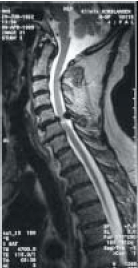

Sie können akut in jedem Alter mit plötzlich einschiessenden Schmerzen an der Wirbelsäule aufteten. Eine fadenförmige oder nicht fadenförmige Ausbreitung der Schmerzen gegen die Arme oder Beine (häufig), selten thorakal (entlang der Rippen) ist möglich. Des weiteren können Teillähmungen oder vollständige Lähmungen vorkommen, die entweder schmerzbedingt sind oder aufgrund von Kompressionen durch ursächliche Prozesse auftreten. Bandscheibenvorfälle (Abbildung 1) sind häufige Ursachen, differentialdiagnostisch müssen auch andere Ursachen in Betracht gezogen werden.

Abbildung 1: Zervikale Diskushernie mit C6-radikulärem Ausfallsyndrom links

In der Abbildung (Sagittalschnitt) sind degenerative Veränderungen dargestellt mit ausgedehnter, medialer bis mediolateraler linksseitiger Diskushernie auf der Höhe C5/6.